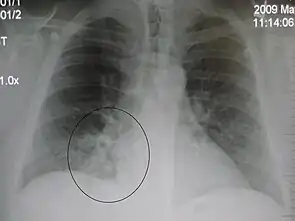

A black and white X-ray picture showing a triangle white area on the left side. A circle highlights the area.

A chest X-ray showing a very prominent wedge-shape bacterial pneumonia in the right lung